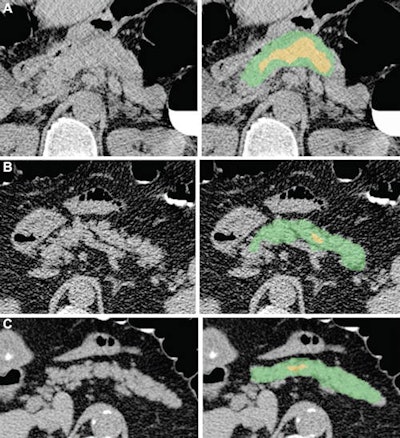

Examples of pancreas segmentations on unenhanced axial abdominal CT images in healthy participants and patients with type 2 diabetes mellitus. Images on left are original CT images, and images on right show segmentations overlaid on the original CT images. (A) Images in a nondiabetic 61-year-old man with average pancreas CT attenuation of 35.50 HU ± 47.96 and pancreatic volume of 97.6 mL. (B) Images of a 59-year-old man with type 2 diabetes who was diagnosed 144 days before CT. Average pancreas CT attenuation was 20.66 HU ± 81.99 and pancreatic volume was 77.10 mL. (C) Images in a 67-year-old man with type 2 diabetes who was diagnosed 595 days after CT. Average pancreas CT attenuation was 18.46 HU ± 48.30 and pancreatic volume was 72.88 mL. The green area indicates full segmentation and the yellow area indicates segmentation after erosion. Image and caption courtesy of the RSNA.Logistic regression analysis then showed that, on average, patients with type 2 diabetes had lower average pancreas, muscle, and liver CT attenuation; higher standard deviation in pancreas CT attenuation; and lower pancreas fractal dimension. A progressive decrease in pancreatic attenuation was found in patients with a greater disease duration.